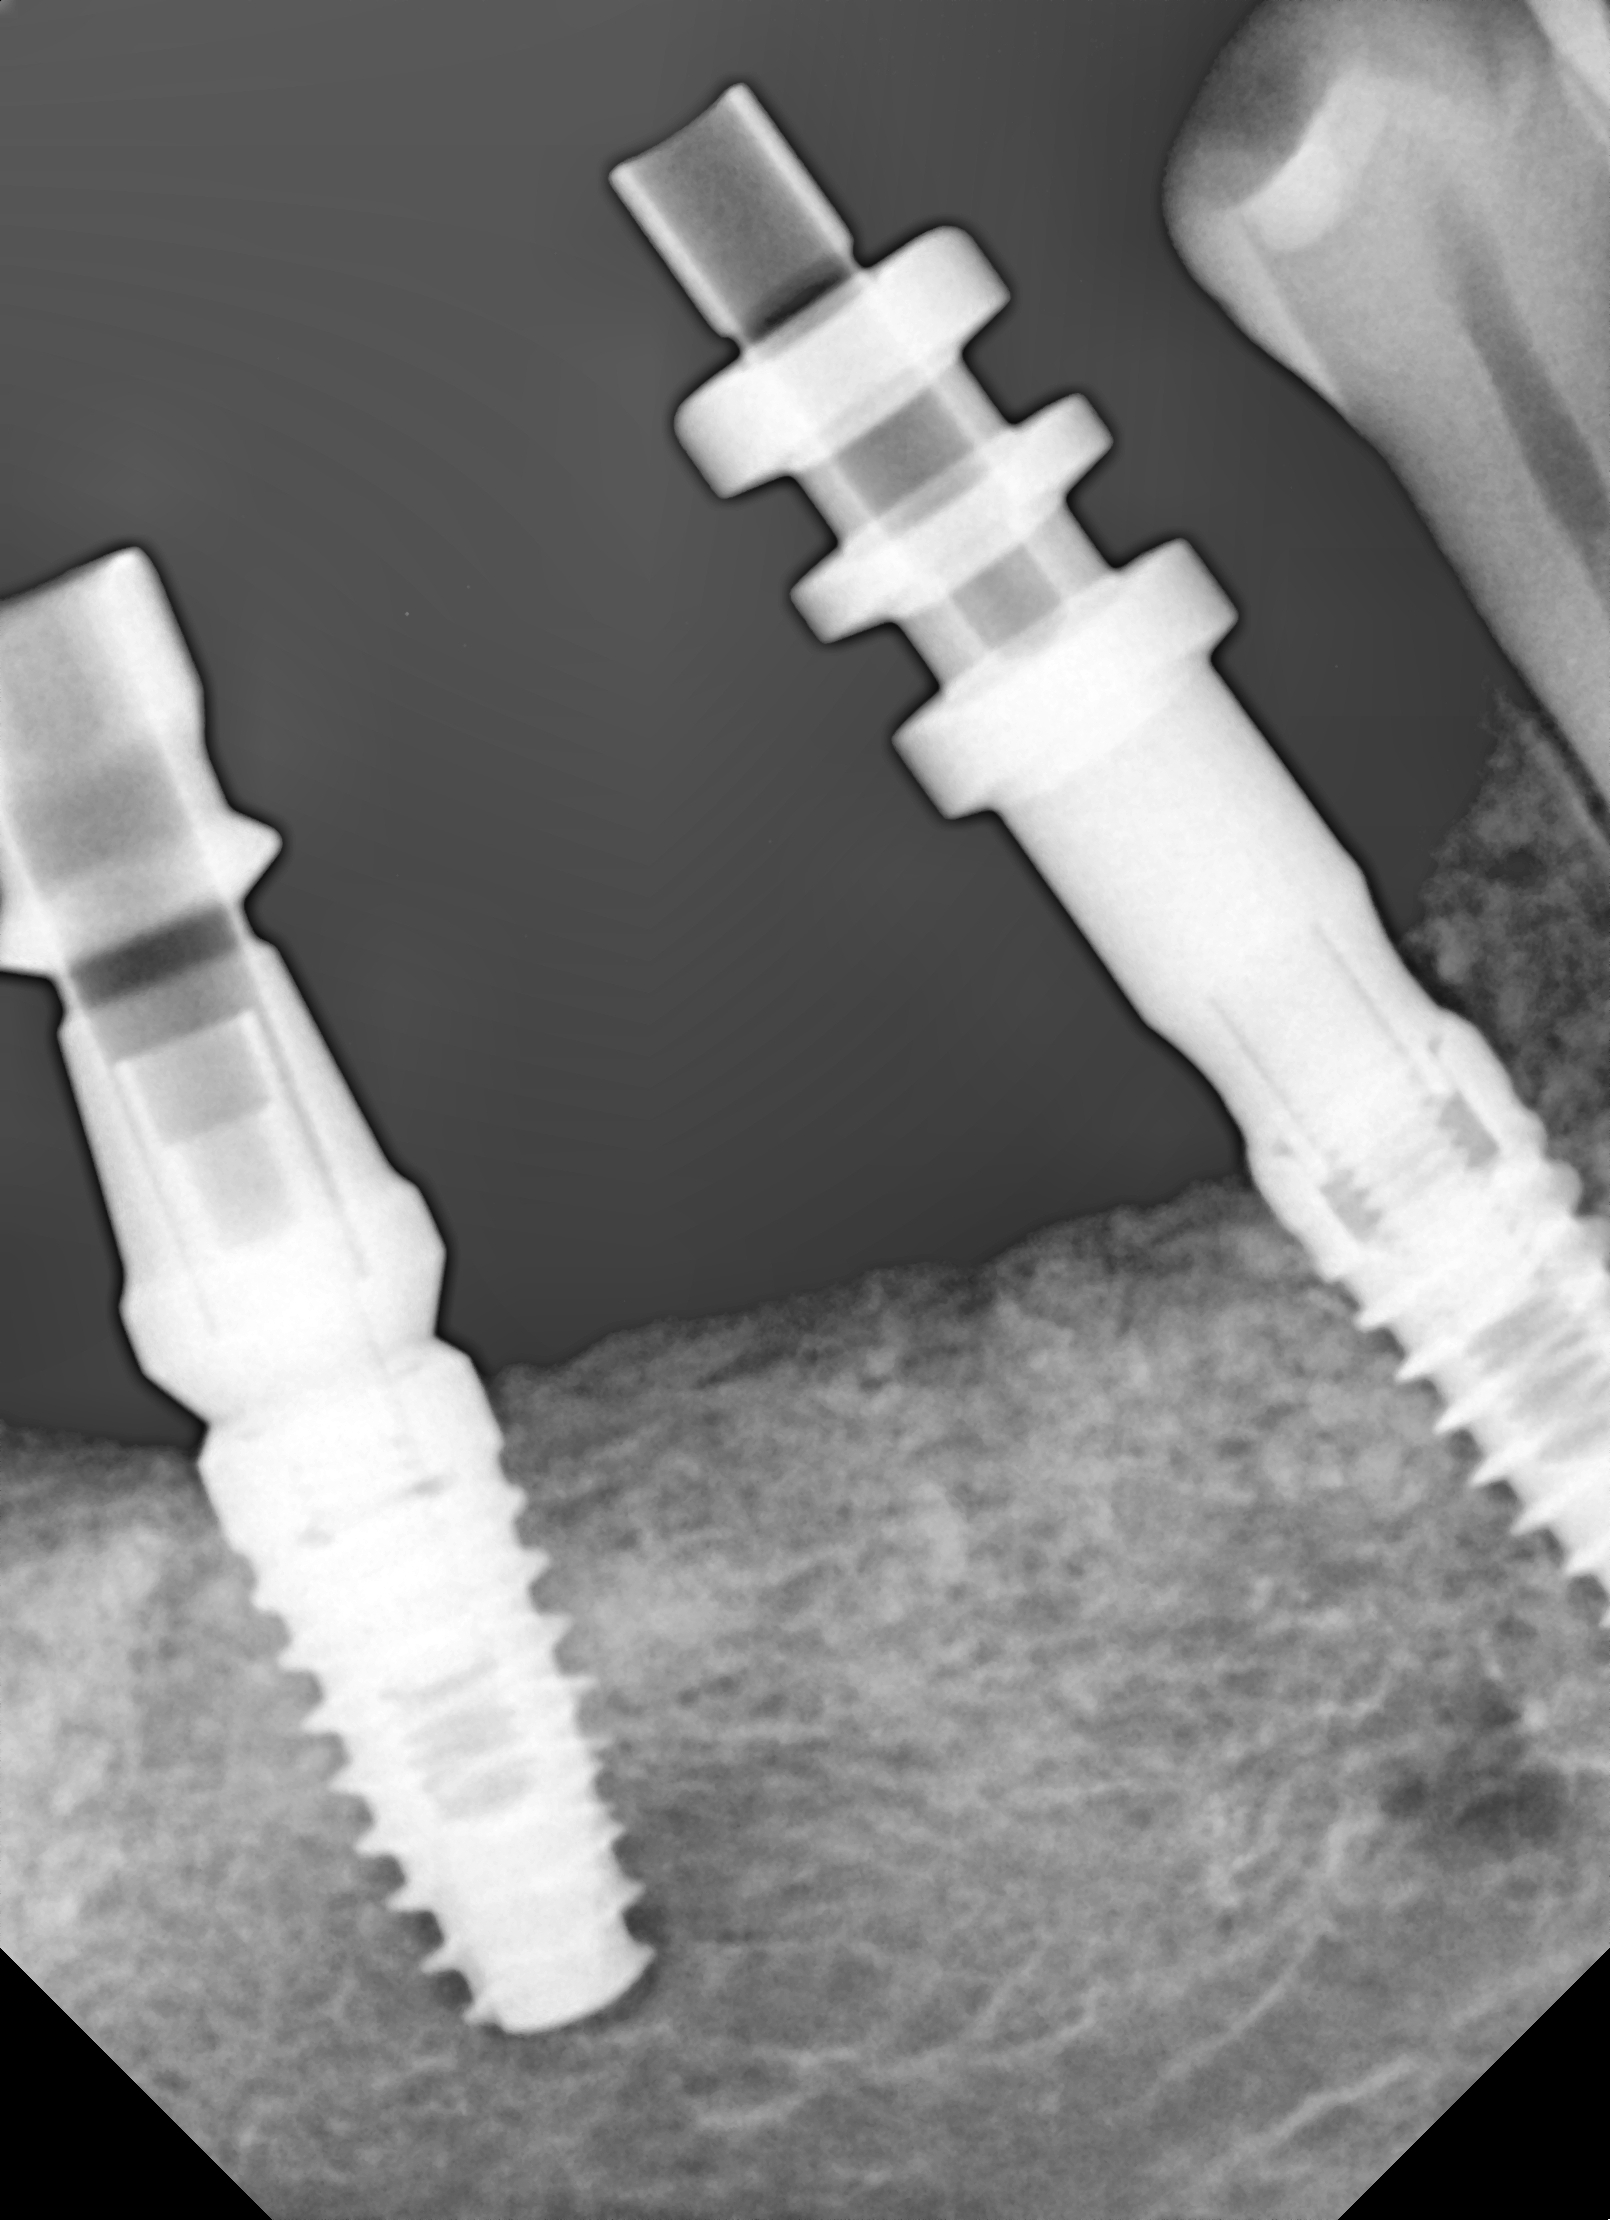

Ryc. 22. Kontrola rtg prawidłowego umocowania śrub gojących.

Ryc. 23. Kontrola rtg umiejscowienia transferów wyciskowych.

Następnie wykonano suprastrukturę protetyczną (most pełnoceramiczny) cementowaną (ryc. 24).

Ryc. 24. Łączniki protetyczne